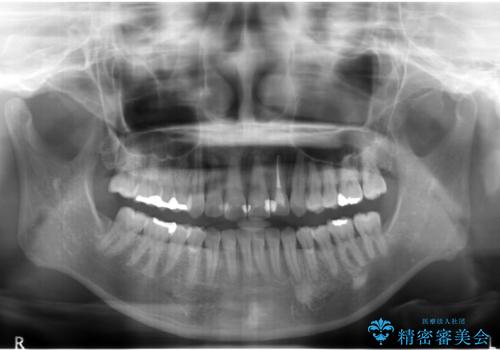

埋まっている奥歯を並べることで、その後ろの倒れ込んだ歯を整直させることができました。

上の歯はマウスピース矯正で、奥歯を後ろに下げて、左のかみ合わせのズレを直しています。

上下とも非抜歯で並べています。

埋まっていた歯をしっかり引っ張り出すことができ、また、前歯の見た目も非常に良くなりました。

ワイヤー矯正を奥歯の部分的に行なっただけで、治療の大半をマウスピース矯正で行うことができ、非常に喜んでいただきました。